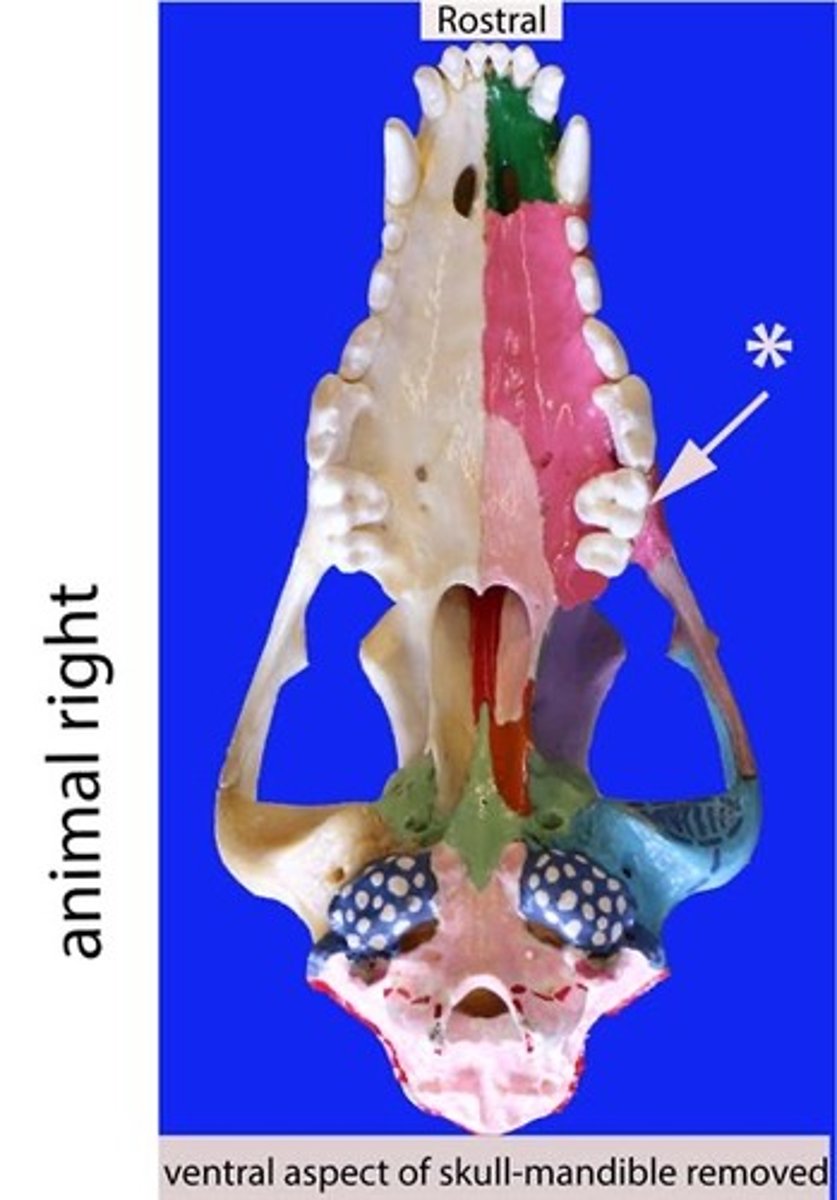

molar

Identify the general type of tooth the arrow is pointing to

Molars

Identify the type of teeth shaded

Molar

Identify the type of tooth indicated by the arrow.